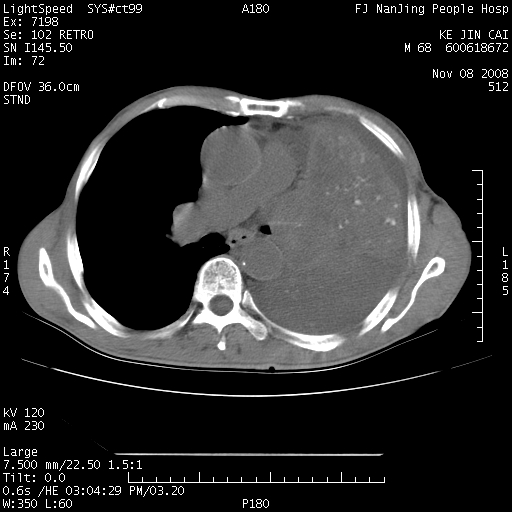

是个很有看头的病例,咋人气那么不旺?没多少人兴趣呢?这个病例几大怪:1   恶性肿瘤侵犯心肌左房怪,心肌一般不会被恶性肿瘤侵犯吧?2   左下肺均匀实变怪,内无含气,有别一般不张实变,含气肺泡完全为液体取代,而非一般不张实变的肺萎陷,冷不丁还以为是肿大的脾脏3   肿瘤本身怪,像tb肺不张4   这么有看头的病例没人气怪。呵呵。

追查病史,咳嗽,患者无发热,血象不高。据说2年前胸片检查怀疑肺ca曾行纤支镜检查,病理未见到癌细胞。无确切资料。

左肺恶性肿瘤侵犯肺动脉,左心房内瘤栓,胸膜转移。